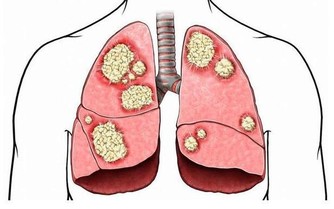

最後,人體的免疫細胞由也是由蛋白質組成,一旦身體缺乏蛋白質就會使得免疫系統功能變差,從而使得免疫力下降。因此,老人缺乏免疫力也會對體質造成影響。